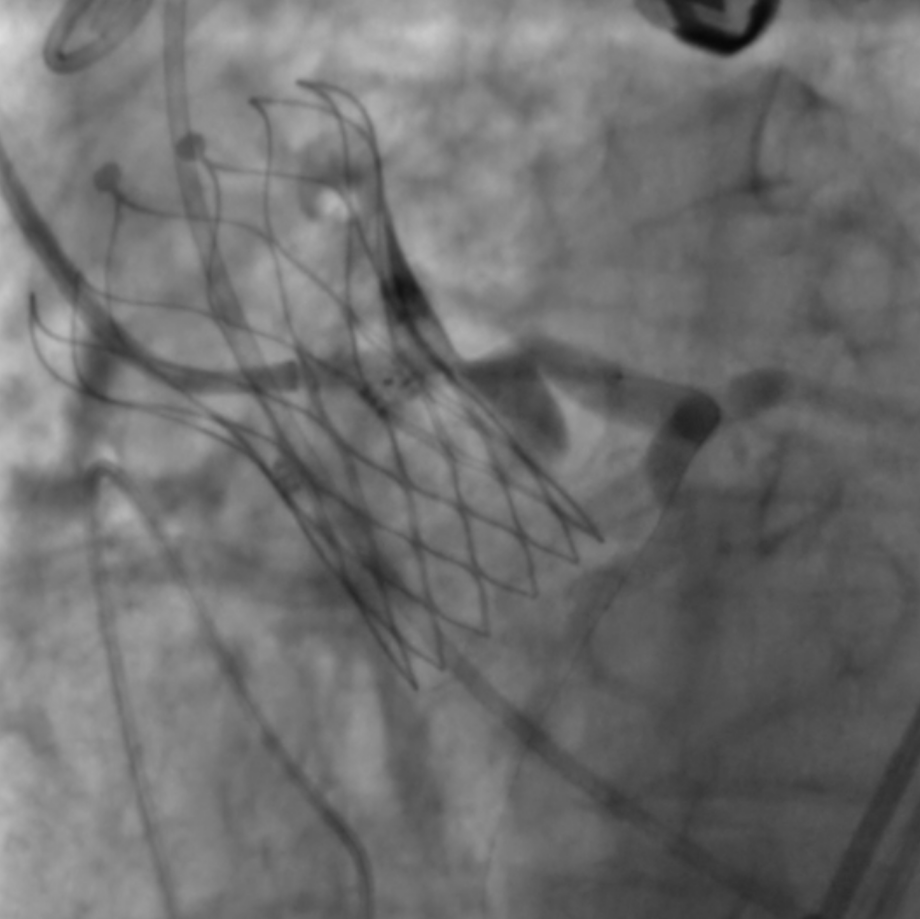

冠脉保护下释放瓣膜

图片

左冠口疑似遮挡

左冠植入4.0x19mm冠脉开窗支架

5.0mm球囊后扩张支架近段

复查左冠开口面积恢复至12.76mm2